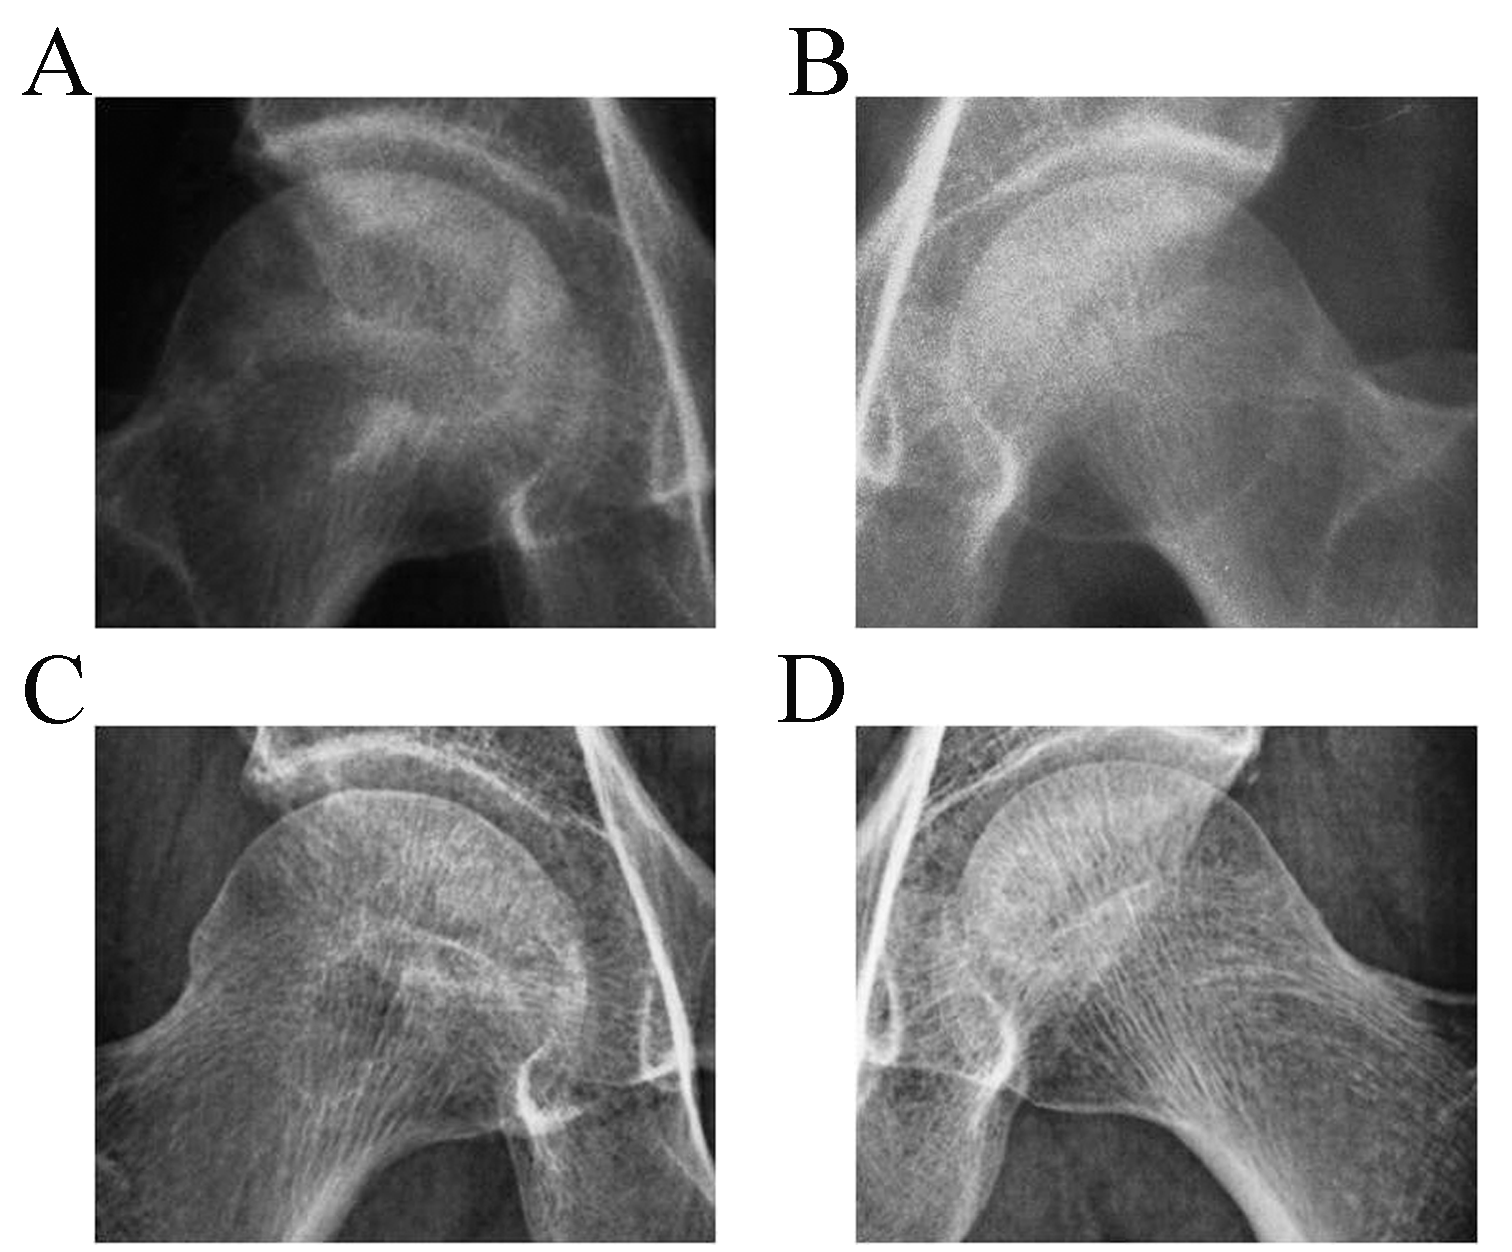

病例2,男,39岁,双侧股骨头坏死2年,治疗12个月后修复,恢复正常工作。

治疗前双侧股骨头轻度变形,可见大面积不规则低密度区,密度不均,骨小梁消失,坏死面积约占90%,关节间隙正常(见图,A,B)。经过12个月的痊愈,股骨头密度基本恢复,小梁结构分布均匀清晰(见图,C,D)。

Case 2, male, 39 years old, Before treatment, there was mild deformation of the bilateral femoral heads, with large areas of irregular low-density visible, uneven density, disappearance of bone trabeculae, necrosis area accounting for about 90%, and normal joint space (see Figure A, B). After 12 months of treatment, the density of the femoral head has basically recovered, and the distribution of trabecular structures is uniform and clear (see Figure C, D).